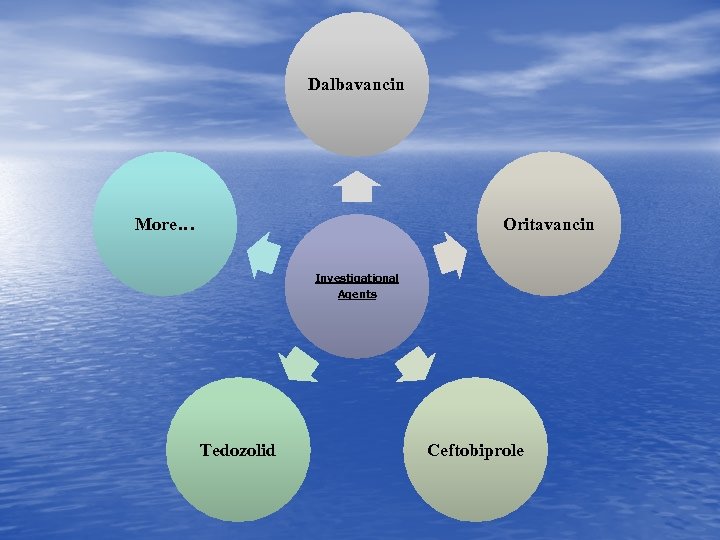

Dalbavancin More… Oritavancin Investigational Agents Tedozolid Ceftobiprole

Dalbavancin More… Oritavancin Investigational Agents Tedozolid Ceftobiprole